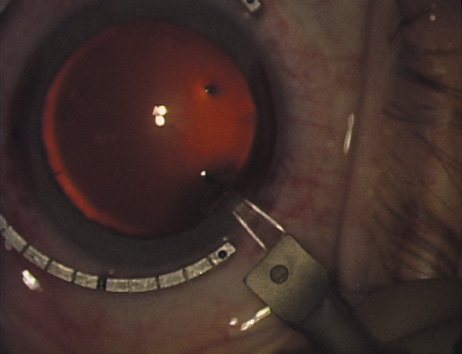

Case 2 is a 79-year-old woman who presented with a very dense left cataract. Her refraction was recorded at −2.25 +2.75 × 125 with a difficult end point. Her manual keratometry and topography measurements were consistent and revealed slightly less than 1.75 D at 120 degrees. Because of the questionable refraction, greater value was placed on the corneal measurements. Based upon the cataract nomogram, the plan was for paired LRIs of 40 degrees to be placed over the steep 120-degree axis (Figs. 1219).

Fig. 15. Total arc length equals 40 degrees. (Reprinted from Hardten DR, Lindstrom RL, Davis EA. Phakic Intraocular Lenses: Principles and Practice. Thorofare, NJ: SLACK Incorporated, 2004, with permission.)

Fig. 16. The starting point of the opposing incision is determined. (Reprinted from Hardten DR, Lindstrom RL, Davis EA. Phakic Intraocular Lenses: Principles and Practice. Thorofare, NJ: SLACK Incorporated, 2004, with permission.)

Fig. 17. The opposing incision is begun. (Reprinted from Hardten DR, Lindstrom RL, Davis EA. Phakic Intraocular Lenses: Principles and Practice. Thorofare, NJ: SLACK Incorporated, 2004, with permission.)

Fig. 18. The incision is completed. (Reprinted from Hardten DR, Lindstrom RL, Davis EA. Phakic Intraocular Lenses: Principles and Practice. Thorofare, NJ: SLACK Incorporated, 2004, with permission.)

Fig. 19. The temporal single-plane clear corneal incision is placed independent of the LRIs. (Reprinted from Hardten DR, Lindstrom RL, Davis EA. Phakic Intraocular Lenses: Principles and Practice. Thorofare, NJ: SLACK Incorporated, 2004, with permission.)